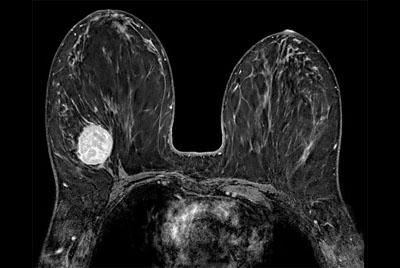

Breast biopsy with dS Sentinelle Breast coil

Dynamic Breast imaging with SmartSpeed AI

Breast 3D and 4D imaging

Breast Ca with T1 perfusion

Breast with Compressed SENSE on BlueSeal magnet

Breast imaging with Compressed SENSE

Breast lesion

Breast imaging using SmartExam

SmartBreast - ds Breast 7ch coil

SmartBreast - ds Breast 16ch coil

dS Breast Adaptive 16ch coil